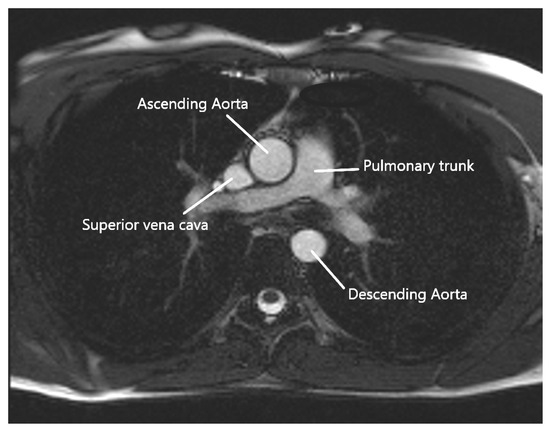

A cardiac MRI was performed before the cardiac surgery to determine, in particular, the aortic compliance. Images were collected using a 3T MRI (Skyra, Siemens Healthineers, Erlangen, Germany), with a specific acquisition in addition to the standard protocol. This acquisition is a FLASH-type sequence undertaken during a short breath-hold in the transverse plane at the level of the pulmonary artery bifurcation, as shown in Figure 1. Since it is less sensitive to noise caused by rapid or turbulent flow at 3T, this sequence was chosen over a steady state free precession (SSFP)–type sequence. This plane allows us to examine both the ascending and descending thoracic aortas. Images at all phases of the cardiac cycle were obtained with a temporal resolution of 20 ms to 34 ms thanks to a retrospective ECG-gating, with the following sequence settings: echo time of 3.42 ms, repetition time of 7.21 ms, flip angle of 12°, spatial resolution between 1.09 × 1.09 mm/pixel, and 1.25 × 1.25 mm/pixel (corresponding to a field of view ranging from 350 mm to 400 mm), and slice thickness of 5 mm. A generalized auto-calibrating partially parallel acquisitions (GRAPPA) was performed, with an acceleration factor of two. A pre-scan normalized filter and distortion correction were also applied.

Figure 1.

Axial MRI at the level of the pulmonary trunk.